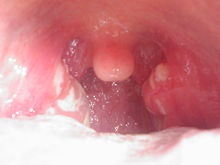

Streptococcal pharyngitis

Streptococcal pharyngitis, also known as strep throat, is an infection of the respiratory tract caused by group A Strep, Streptococcus pyogenes, a gram-positive, cocci, beta-hemolytic (lyses blood cells) bacteria.[42] It is primarily spread by direct contact and the transfer of fluids via oral or other secretions and manifests largely in children.[42] Common symptoms associated with streptococcal pharyngitis include sore throat, fever, white excretions at the back of the mouth, and cervical adenopathy (swollen lymph nodes underneath the chin and around the neck area).[43] Streptococcal pharyngitis can lead to various complications[44] and recurrent infection can increase the likelihood. In many of these, lack of treatment[45] and the body's immune response is responsible for the additional adverse reactions.[46] These include:[44]